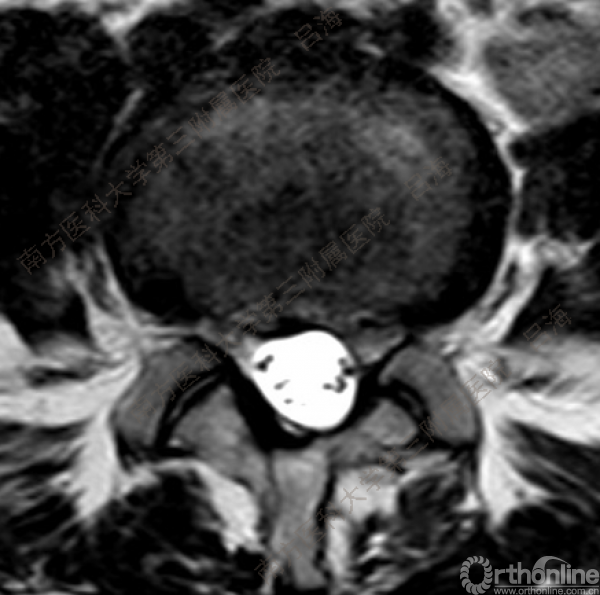

随着社会老龄化进程加快,胸腰椎退行性病变的治疗已经成为脊柱学术界的一个热点话题。MIS-TLIF手术可以治疗多种不同的胸腰椎退行性疾病,南方医科大学第三附属医院吕海教授结合病例为我们一一展示了该术式在治疗不同胸腰椎疾病时的具体手术过程。